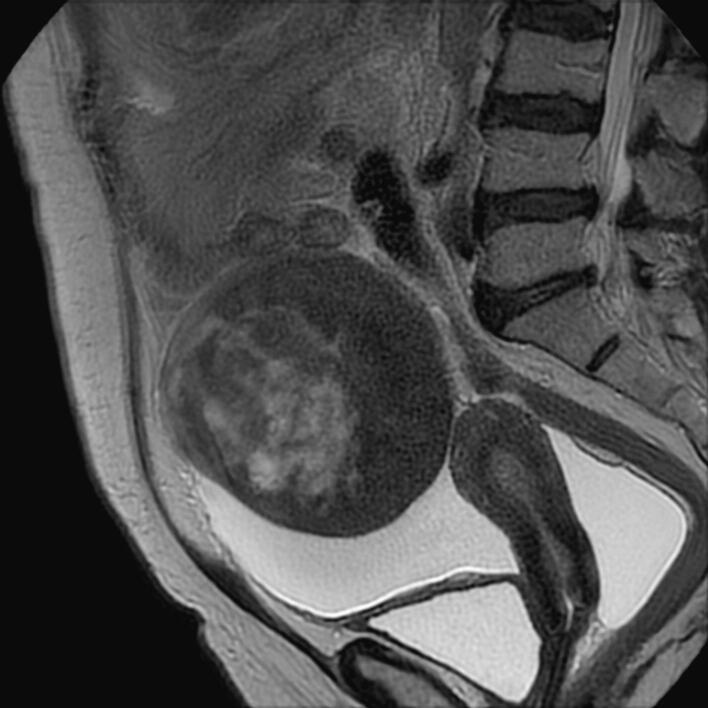

We report the case of a 60-year-old woman who was referred to our unit, because of abdominal bloating, sporadic pelvic pain and abdominal distension. Ultrasound showed a heterogeneous mass over the right adnexa with ascites. Serum tumour markers were within normal limits. During surgery, a total abdominal hysterectomy plus bilateral adnexectomy was performed. The final histopathological findings showed a well-differentiated fibrosarcoma. The patient was followed up regularly and no recurrence was seen 2 years after surgery.

我们报告一例60岁女性病例,该患者因腹胀、散发性盆腔疼痛和腹部膨隆被转诊至我院。超声检查显示右侧附件区有一不均质肿块伴腹水。血清肿瘤标志物在正常范围内。手术中,进行了全腹子宫切除术加双侧附件切除术。最终组织病理学检查结果显示为高分化纤维肉瘤。患者接受定期随访,术后2年未见复发。